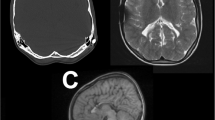

Three WHIPS patients had pre- and post-operative T2* MRI, two had pre- and post-operative SWI MRI and three had pre- and post-operative CT for WHIPS identification. WHIPS varied greatly in number ranging from 1 to innumerable haemorrhages. WHIPS were identified in the periventricular white matter in 4/8 cases (Fig. 2), deep white matter in 3/8 cases (Fig. 2), cortico-subcortical region in 5/8 cases (Figs. 3) and 3/8 patients had involvement of two or more regions (Figs. 2 and 3). Ovoid lesions were seen in 5/8 cases and ranged from < 5 mm to 15 mm in size. Punctate lesions were seen in 4/8 cases and tended to be very small < 5 mm. One patient (case 5, Table 3) had innumerable severe confluent fan-shaped WHIPS, reminiscent of the “iris sign” in deep medullary venous haemorrhage (Fig. 4), however the severity of the WHIPS in this patient may have been compounded by the underlying COL4A1 mutation [11]. This same patient also demonstrated progression of WHIPS between CT studies performed day 2 and day 11 post insertion of a right trans-parietal VP shunt (Fig. 5), again this progression could have been confounded by the underlying COL4A1 mutation. In terms of lobar distribution in the brain 5/8 had involvement of the frontal lobes, 5/8 had parietal involvement, 3/8 had temporal involvement and 2/8 had occipital lobe involvement, with more than one lobe involved in 3/8 patients. The deep grey matter structures and infratentorial brain were not involved in our WHIPS cohort. The more severe the WHIPS the longer the time to shunting, the two patients with innumerable WHIPS were associated with shunting 24 and 35 days after identification of hydrocephalus and the patient with 11 WHIPS waited 63 days for CSF diversion after hydrocephalus was diagnosed. The WHIPS patients with the largest haemorrhage burden all had shunting for post-haemorrhagic hydrocephalus. This information is summarised in Table 3. In terms of other complications after shunting other than WHIPS development, 2/8 WHIPS cases had new bilateral subdural collections, notably there were no cases of subpial haemorrhage identified in the WHIPS cohort.

(a) Axial CT performed day 2 post right transparietal VP shunting for post-haemorrhagic hydrocephalus and porencephalic cysts due to an underlying COL4A1 mutation (same patient as Fig. 4) shows bilateral frontal WHIPS in A (white arrows) with evidence of ependymal and white matter calcifications (red arrows). (b) Axial CT performed 11 days later shows progression of bilateral frontal WHIPS and new right occipital WHIPS (blue arrowheads) surrounded by progressive low attenuation oedema. Bilateral enlarging CSF attenuation subdural collections are also evident in B distorting the parenchyma

We have expanded the neuroradiological characterization of WHIPS, revealing that these haemorrhages exhibit a spectrum from being singular to innumerable, distributed throughout the supratentorial brain parenchyma—from the periventricular white matter and deep white matter to the cortico-subcortical regions. Our findings indicate WHIPS involvement occurs across all lobes of the supratentorial brain, with noteworthy sparing of the deep grey matter structures and infratentorial brain in our studied cohort. In one of our WHIPS cases, the haemorrhages displayed a fan-shaped confluent and diffuse pattern, reminiscent of the “iris sign” observed in deep medullary venous haemorrhage, this case also showed large post-operative bilateral subdural haemorrhages [11]. This “iris sign” was also seen in Figs. 2 and 3 of the original description of this entity by Choi et al. [7], both of these reported cases also demonstrated bilateral subdural collections after shunting. Notably, our patient with the “iris sign” also illustrated the progressive nature of these haemorrhages, with a significant increase in haemorrhage burden over a 9-day period (see Fig. 5), a facet not previously detailed in descriptions of this entity. Furthermore, our observations reveal that more extensive WHIPS cases in our cohort were associated with a longer duration between the initial identification of hydrocephalus and the commencement of shunting, all occurring in patients with post-haemorrhagic hydrocephalus.